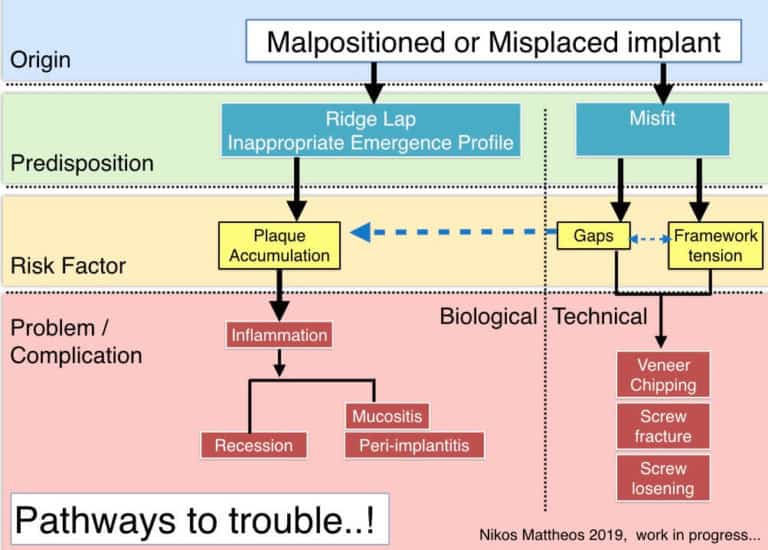

Lesson Nr. 2: what we diagnose as “complication” might often be the result of a hidden (and often iatrogenic) predisposition…!

…and here some work in progress!

The idea is to map in a flowchart some of the most common “origins” predisposing to problems by exposing implant treatment to known biological or technical risks, finally resulting in complications. Any suggestions more than welcome!

But what if you place an implant in a patient with periodontitis? Or a patient with deficient practice / understanding of oral hygiene? What if you place an implant in unfavorable prosthetic position resulting in an uncleanable prosthesis? In all the cases above, the implant is “predisposed” to trouble. In the terminology of medical devices this would make the implant used “off-label”. Problems will surface sooner or later and then we will pack it together in a summative number as complications. But how many of the implants reported in the literature with complications could actually have been “off-label”? For example, how many studies reporting prevalence of peri-implantitis also report how many of the prostheses were uncleanable? As of today, I know only one (3). This fact might partly explain the wide range of prevalence found in different studies and environments. Complications will occur even when all conditions of use are met, but if we add on top the problems of implants that are predisposed, do we get a fair picture of the problem? Predisposing factors can also be technical. In a series of recent studies (4,5) we found that even a small vertical misfit of 100μm has the potential to increase the risk of veneer chipping by multifold in small-medium span implant prostheses.